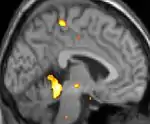

Positron emission tomography (PET) scans indicate the brain areas which are activated during attack only, compared to pain free periods. These pictures show brain areas that are active during pain in yellow/orange color (called "pain matrix"). The area in the center (in all three views) is specifically activated during CH only. The bottom row voxel-based morphometry (VBM) shows structural brain differences between individuals with and without CH; only a portion of the hypothalamus is different.[36]

| Positron emission tomography (PET) shows brain areas being activated during pain. | ||

| Voxel-based morphometry (VBM) shows brain area structural differences. | ||